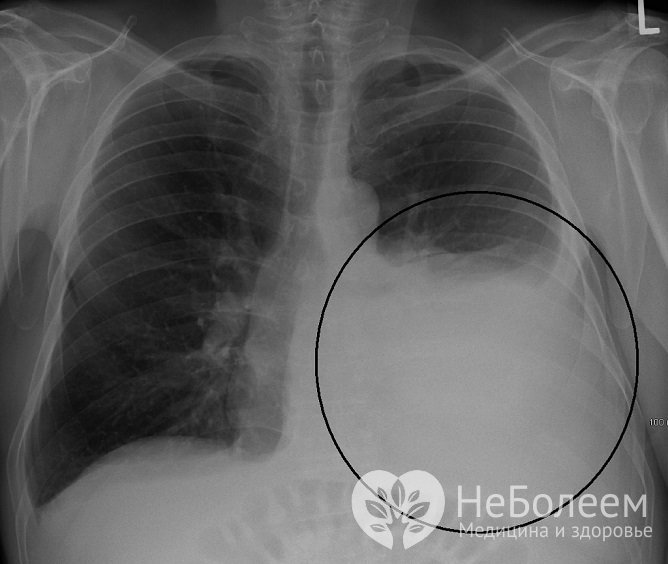

- рентгенологическое исследование в прямой и боковой проекциях;

Гидроторакс на рентгеновском снимке

Гидроторакс на рентгеновском снимкеТакие лабораторные методы исследования, как общий анализ крови и мочи, биохимический анализ крови диагностической ценности для подтверждения гидроторакса не имеют. С целью дифференциальной диагностики характера жидкости (транссудат, экссудат) осуществляется проба Ривальты, позволяющая подтвердить или опровергнуть воспалительный характер содержимого гидроторакса.